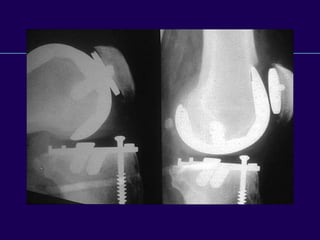

Complications in Total

Knee Arthroplasty

Periprosthetic Fractures

Infected Total Knee

Arthroplasty

Supracondylar

Fractures of the

Femur

After Total Knee

Supracondylar Fractures

After TKR

l Notching of the femoral cortex

l Osteoporosis

l Prolonged steroid use

l Preexisting neurologic

disorders

l Plates / Screw fixation

l Intramedullary rods

l Rush pins

l External fixation

l Primary arthrodesis

l Revision arthroplasty

Operative Method